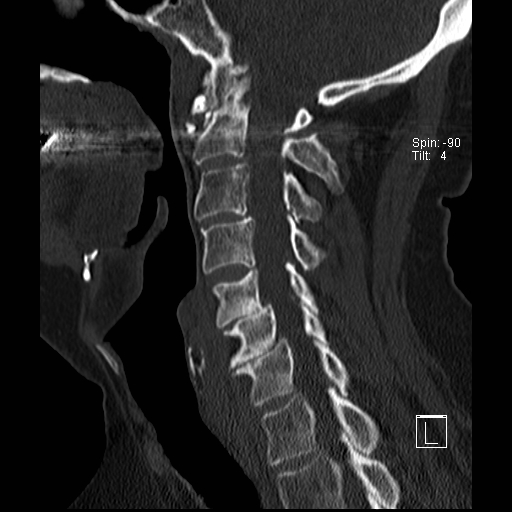

Trật khớp đội – trục

Cột sống cổ thường bị ảnh hưởng trong viêm khớp dạng thấp và có thể biểu hiện dưới dạng mất vững khớp đội – trục, trật khớp dưới trục hoặc lồng nền sọ kèm theo sụt lún sọ não.

Sụt lún sọ não xảy ra khi mỏm răng xâm lấn vào lỗ chẩm.

Trật khớp đội – trục là một biến chứng quan trọng và có thể đe dọa tính mạng của viêm khớp dạng thấp. Tình trạng này được xác định khi khoảng cách giữa mỏm răng C2 và cung đốt đội vượt quá 3 mm. Nguyên nhân là do lỏng lẻo dây chằng do viêm.

Mất vững tại khớp này có thể gây ra nhiều triệu chứng thần kinh do chèn ép tủy sống.

Hình ảnh

Khi cúi cổ, khoảng cách giữa mỏm răng và mặt sau cung trước đốt đội bị giãn rộng (14 mm) (bình thường ≤3 mm).